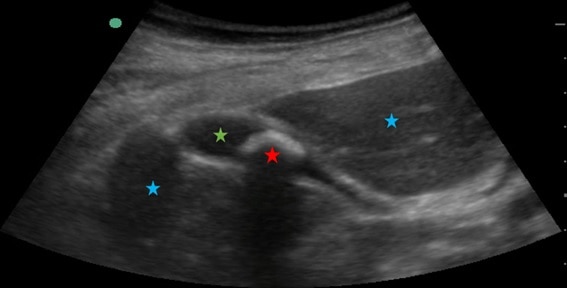

En ecografía, podemos distinguir las estructuras del cuerpo siempre que sean de impedancias diferentes (es decir, que exista una interfase entre ellas).

En la imagen siguiente, podemos distinguir el hígado (estrella azul, de una densidad determinada) de la vesícula (estrella verde, de un contenido líquido, de densidad menor) de la litiasis biliar (estrella roja, formada por calcio, de una densidad mucho mayor a las anteriores) porque entre cada una de estas estructuras se forma una interfase, al tener densidades (y por tanto impedancias) distintas.